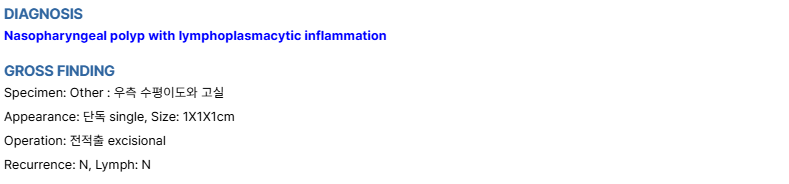

[수술 후 조직검사 결과]

조직검사 상에서 염증성 폴립으로 확인되어, 추가적인 절제나 수술 없이 관리할 수 있었습니다.